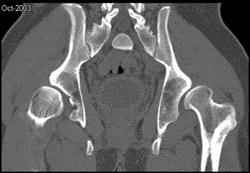

问题 男,23岁,行走跛行,外展受限,两下肢不等长,结合图像,最可能的诊断是 ( )

选项 A、先天性髋内翻 B、髋关节结核 C、髋关节后脱位 D、髋关节前脱位 E、髋关节中心脱位

答案 C